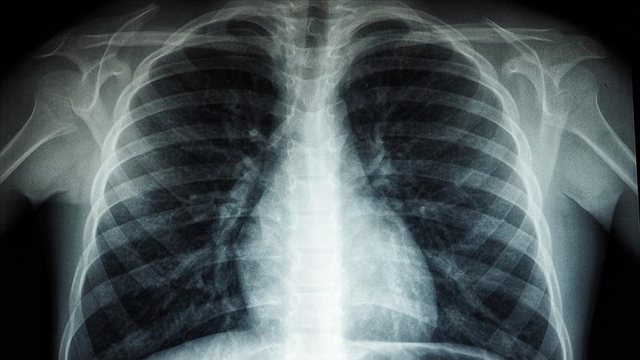

Drejtori Rajonal i Organizatës Botërore të Shëndetësisë (OBSH) për Evropën, Hans Kluge, njoftoi se 1 milion njerëz vdesin çdo vit nga tuberkulozi, “sëmundja infektive më vdekjeprurëse në botë”

“Tuberkulozi është sëmundja infektive më vdekjeprurëse në botë, duke vrarë 1 milion njerëz çdo vit”, tha Kluge.

Ai ka shtuar se rezistenca ndaj ilaçeve, bashkë-infeksioni tuberkuloz-HIV, qasja e pabarabartë në kujdesin shëndetësor dhe financimi i pamjaftueshëm po e përkeqësojnë më tej krizën.

Në “Raportin Global të Tuberkulozit 2025”, të botuar më 12 nëntor, OBSH-ja raportoi se më shumë se 1.2 milionë njerëz kanë humbur jetën nga tuberkulozi në vitin 2024, dhe afërsisht 10.7 milionë njerëz u prekën nga sëmundja, transmeton oranews.